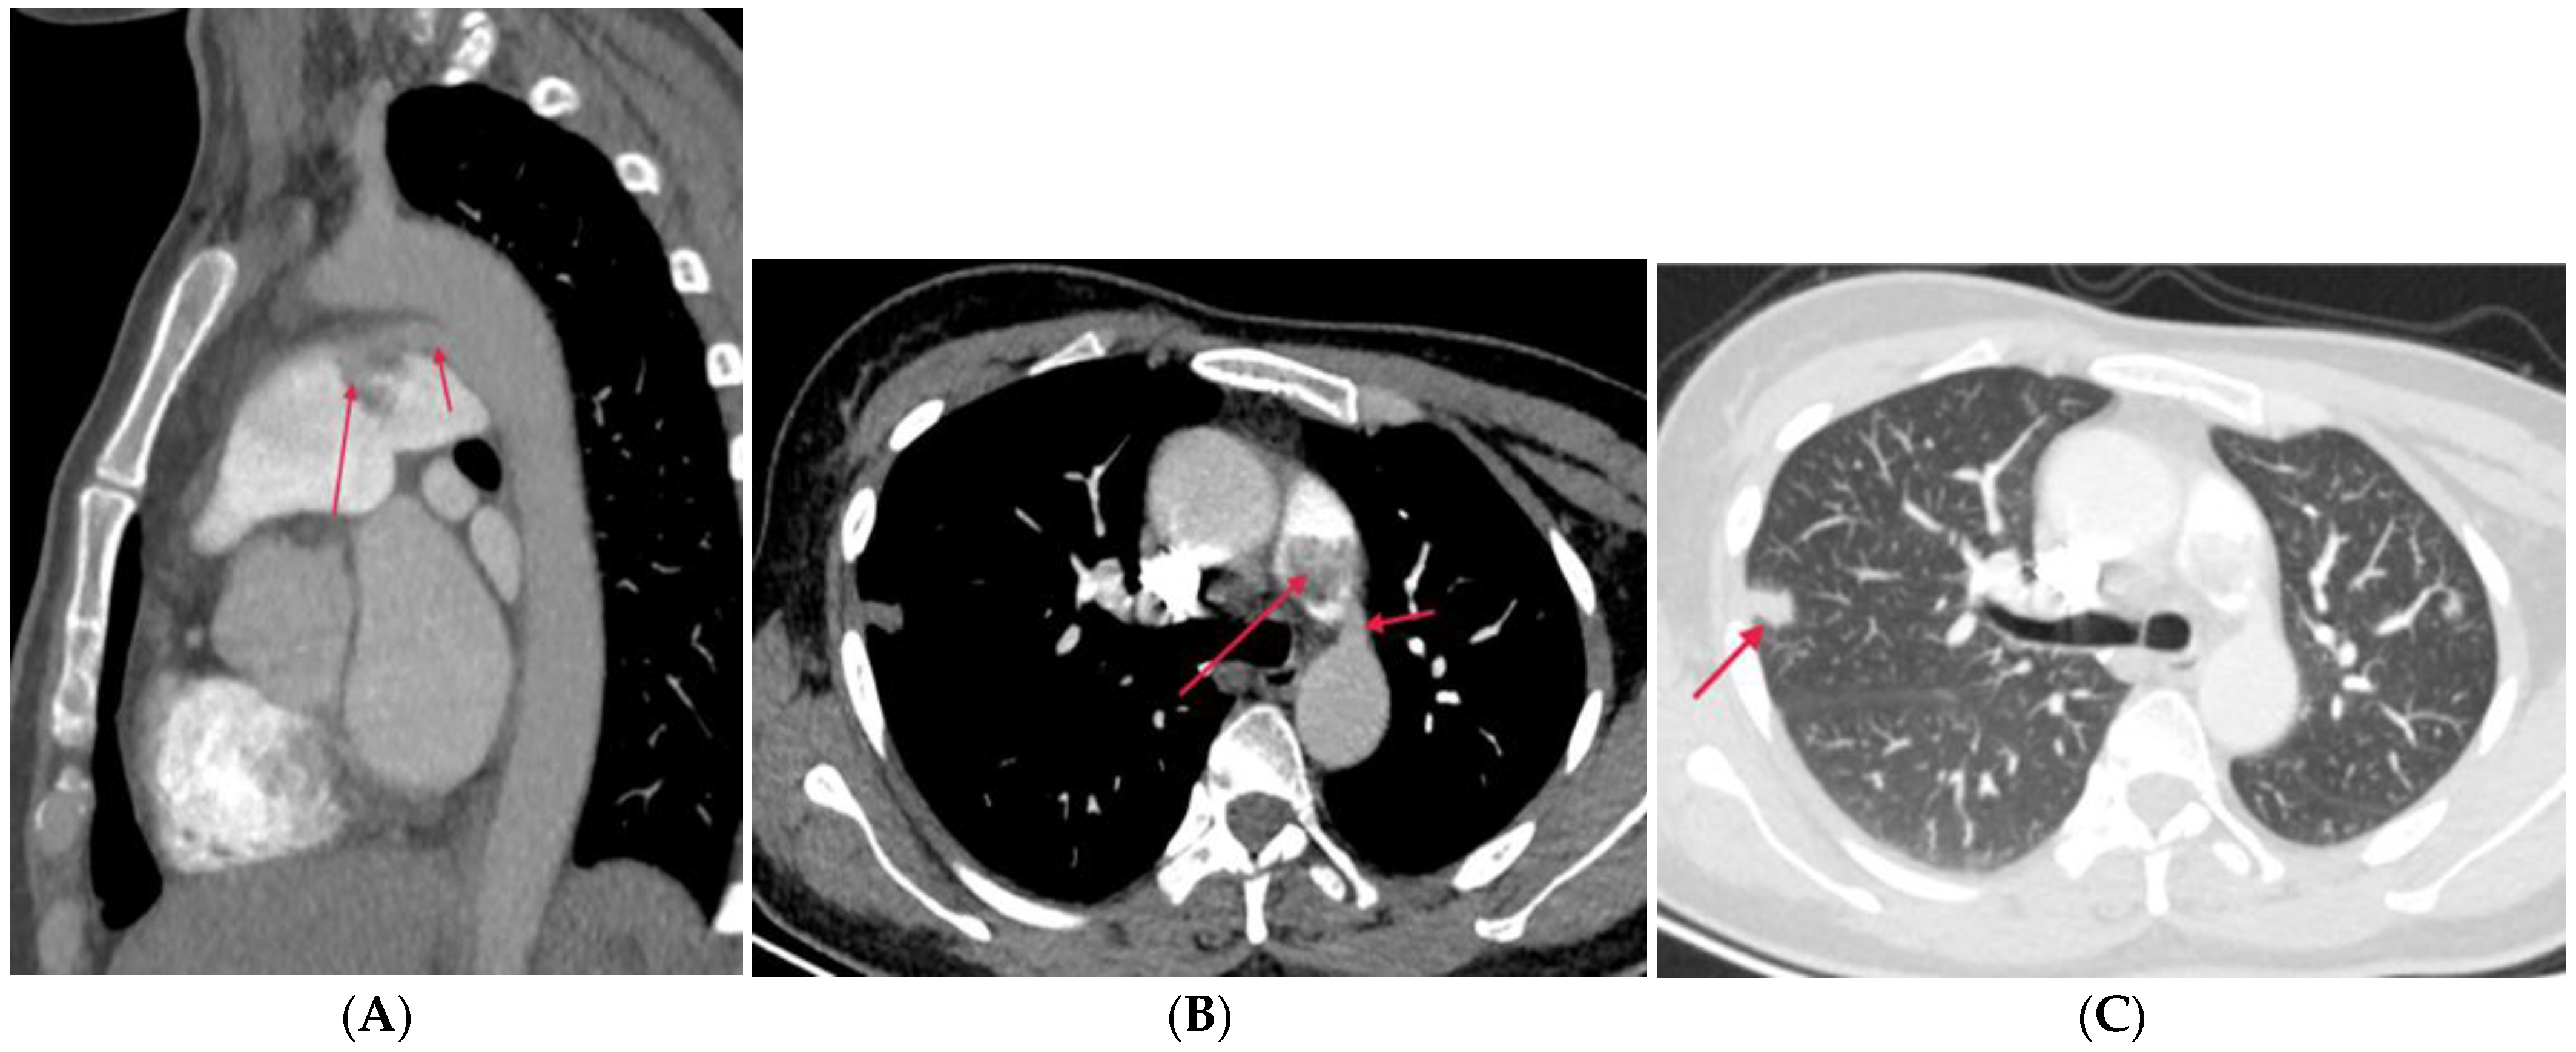

4.3. Extra-Luminal Abnormalities

4.3.1. Fibrosis Mediastinitis (FM)

4.3.2. Tumors Causing Pulmonary Artery Stenosis

4.3.3. Aortic Aneurysm